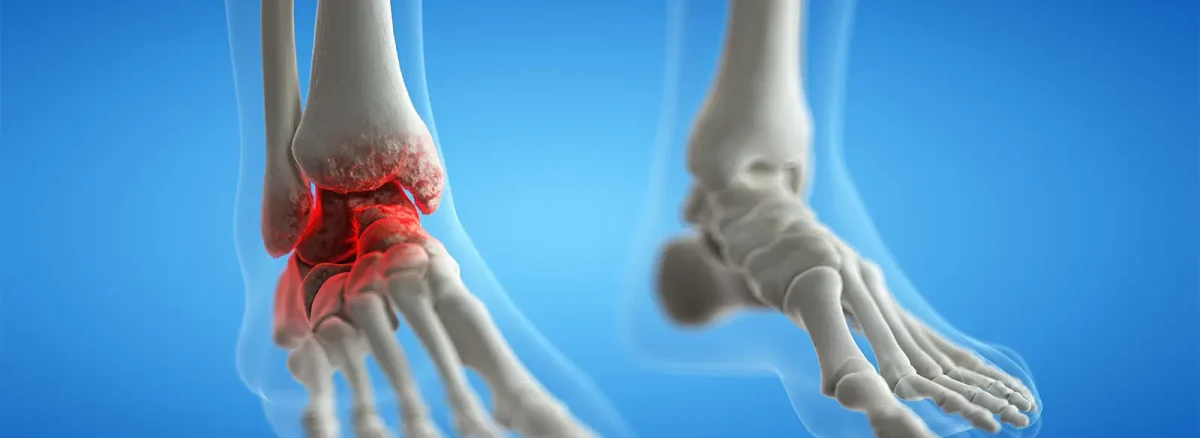

مچ پا یکی از مفاصل پرکاربرد بدن است که باید در طول عمر ما وزن بدن را تحمل کرده و ضربات ناشی از راه رفتن و دویدن را جذب کند. اما وقتی غضروف این مفصل حیاتی دچار ساییدگی میشود، بیماری دردناکی به نام آرتروز مچ پا شکل میگیرد. این بیماری نه تنها باعث درد و سفتی میشود، بلکه کیفیت زندگی و توانایی انجام فعالیتهای ساده روزمره را به شدت کاهش میدهد.

آرتروز مچ پا نوعی آرتریت استئووآرتریت (ساییدگی و پارگی) است که در آن، لایه غضروفی که انتهای استخوانها را میپوشاند، به مرور زمان از بین میرود. این امر باعث میشود استخوانها مستقیماً روی هم ساییده شوند و درد، تورم و محدودیت حرکتی ایجاد کنند.